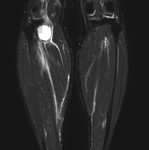

[画像診断]膝窩嚢胞(Baker's cyst)の破裂、MRI所見について 2011-04-18